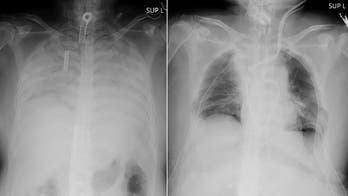

Transplants April 9, 2021 COVID-19 patient receives lung transplant from living donors Doctors in Japan announced Thursday they have successfully performed the world’s first transplant of lung tissue from living donors to a patient with severe lung damage from COVID-19.